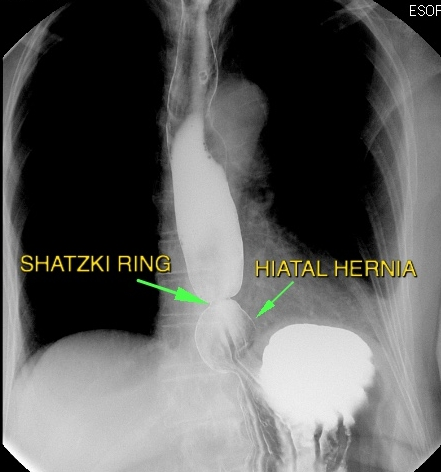

- Schatzki-Ring (distal, meist mit Hiatushernie) → Dysphagie für feste Speisen.

- Diagnostik: Breischluck oder Endoskopie.